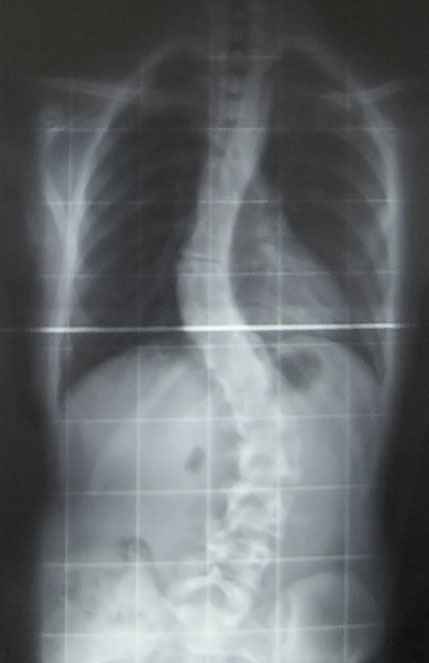

Столичные врачи успешно провели операцию по коррекции тяжелого сколиоза у 12-летней девочки из Омска в Российской детской клинической больнице.

Угол деформации позвоночника составлял 115 градусов.

Специалисты установили транспедикулярные винты, соединив их стержнями, и внесли коррекции в трех плоскостях. Они также устранили реберный горб и дисбаланс плечевого пояса, улучшив функции органов грудной клетки.